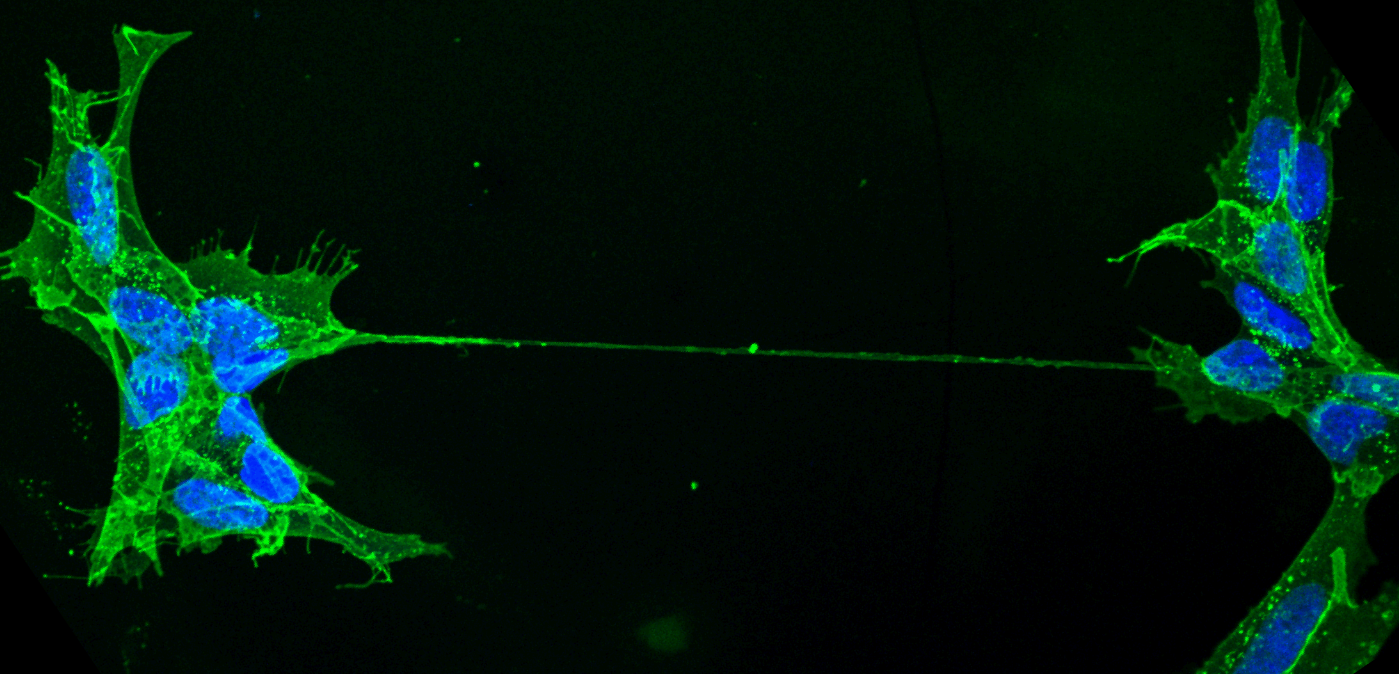

▲ 通过纳米管连接的人类神经元细胞IT之家注:隧道纳米管是存在于细胞间的膜管样结构,可以在细胞间传输激素、酶、细胞器和囊泡等物质。但由于隧道纳米管结构易破坏、存在时间短以及形成后不稳定,观察其动态形成与功能存在一定难度。

▲ 细胞与纳米管相连自 2003 年德国与瑞士团队首次在体外实验中观察到 TNT 以来,科学界对这一结构的生物学意义长期存在争议。为突破研究瓶颈,巴斯德研究所膜运输与发病机制单元负责人 Chiara Zurzolo 教授率领由 15 名青年科学家组成的国际团队,选用具有透明特性的斑马鱼胚胎作为研究对象,通过荧光标记技术与活体显微成像技术(包括 3D 活细胞荧光显微镜、超分辨率显微镜及冷冻电镜),首次捕捉到活体生物中 TNT 的动态形成过程。

研究发现,斑马鱼胚胎细胞间延伸出的细长中空管状结构确认为 TNT,并观察到线粒体通过该通道在细胞间转移的现象。“这不仅证实 TNT 在活体内的存在,更表明其对胚胎健康发育具有重要作用。”Zurzolo 强调。此前,科学界仅在体外实验中观察到此类现象。